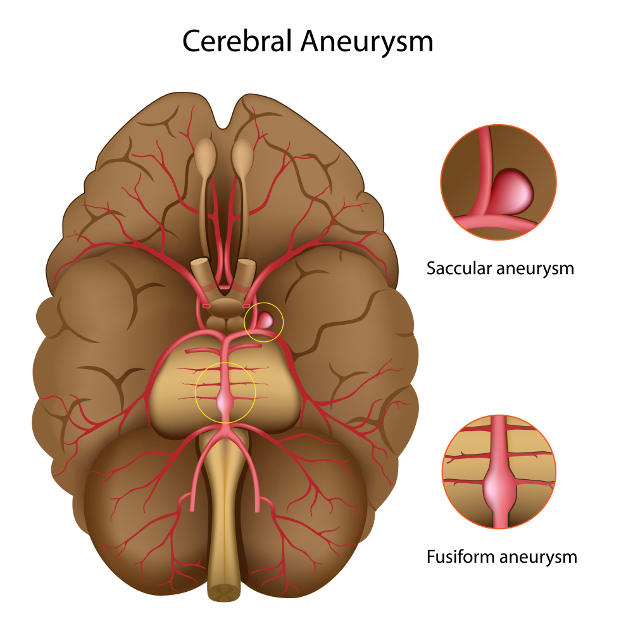

Um aneurisma cerebral é uma pequena “bolha” que se forma na parede de um vaso do cérebro. Essa parte da parede fica mais fina e mais frágil, como um ponto de fraqueza no encanamento.

É quando existe uma parte mais fraca na parede do vaso do cérebro, que forma uma bolha, como se fosse uma bexiga ou um ponto frágil no cano.

Dizemos aneurisma não roto quando essa “bexiga” não estourou.